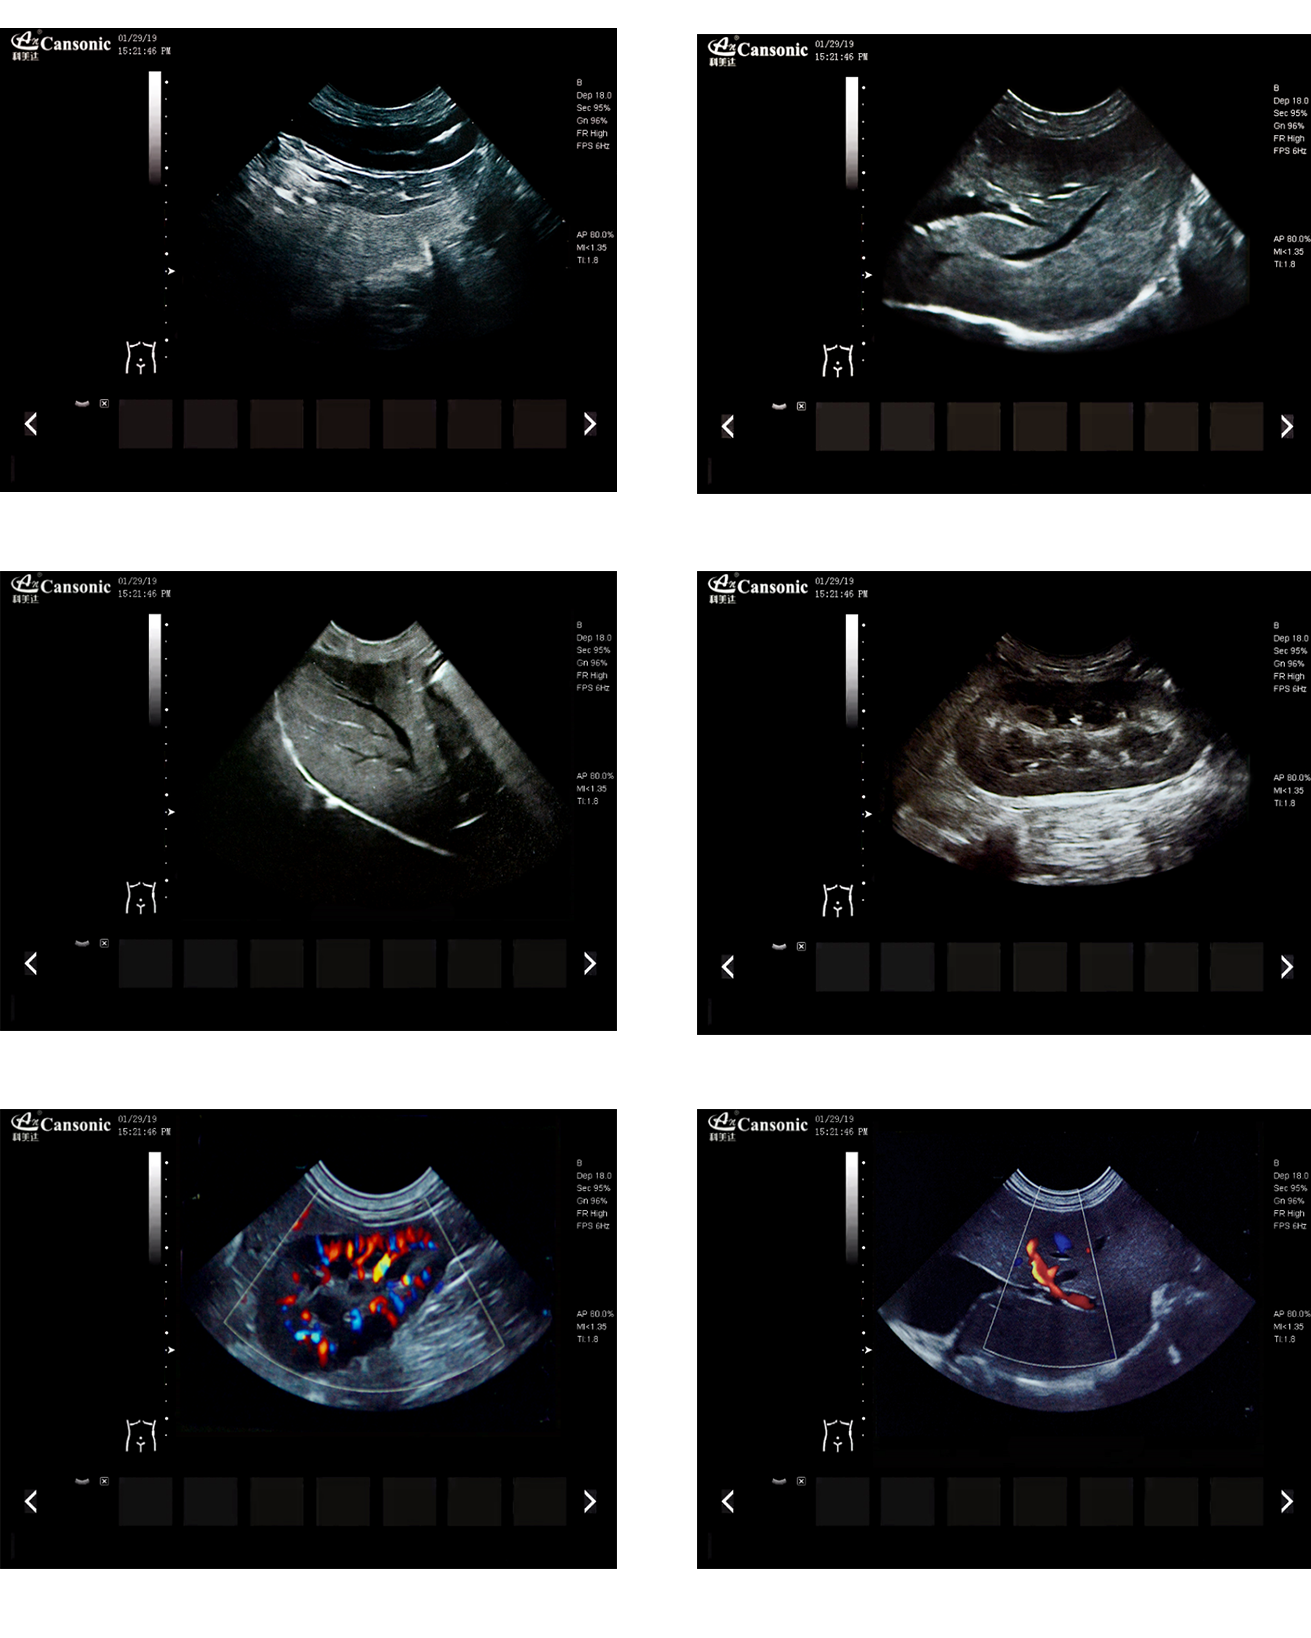

臨床圖示

1、薈萃前沿成像技術(shù),實(shí)現(xiàn)高精與靈便的完美融合,提供完整的動物彩超診療方案

2、專業(yè)的獸用測量軟件,簡捷的工作流,適合犬、貓、馬、牛、羊等 各類大小動物

3、iClear斑點(diǎn)噪聲抑制抑制噪聲干擾,使動物組織結(jié)構(gòu)更清晰

4、具有廣泛的動態(tài)范圍,顯示出色的組織均勻性,減少了偽影及噪聲

5、精細(xì)血流識別技術(shù),增加了可疑病變更多的信息分析

6、先進(jìn)的算法帶來清晰的穿刺針顯示,降低穿刺活檢操作難度